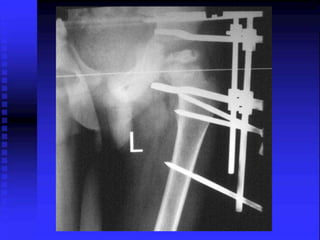

Case-3 A 5-y-oldmale tripped and fell down the last 4 stairs. He went on to play basketball with no pain. At home he complained of right hip pain. At night he woke up C/O of right hip pain. Taken to ER , he had normal ROM of his extremities including the right leg. However when he moved it, he said it did hurt. Radiographs of pelvis and hips were obtained

• 105.

• 106.